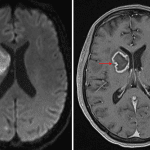

CT

- Areas of hypoattenuation in the anterior right basal ganglia/anterior limb of the right internal capsule and in the right frontal subcortical white matter with mild corresponding local mass effect

MRI

- Multifocal areas of parenchymal restricted diffusion involving the bilateral cerebral and cerebellar hemispheres

- The largest lesion is located in the anterior right basal ganglia/anterior limb of the right internal capsule, which measures 3 x 2.5 x 2.3 cm, demonstrates peripheral enhancement which is incomplete along its ependymal margin, and demonstrates central restricted diffusion

- Linear enhancement extends along the superior margin of the right lateral ventricle

- Many of these lesions demonstrate peripheral susceptibility artifact

- Surrounding vasogenic edema, particularly involving the right basal ganglia and right frontal subcortical lesions

- No substantial midline shift or evidence of herniation or hydrocephalus